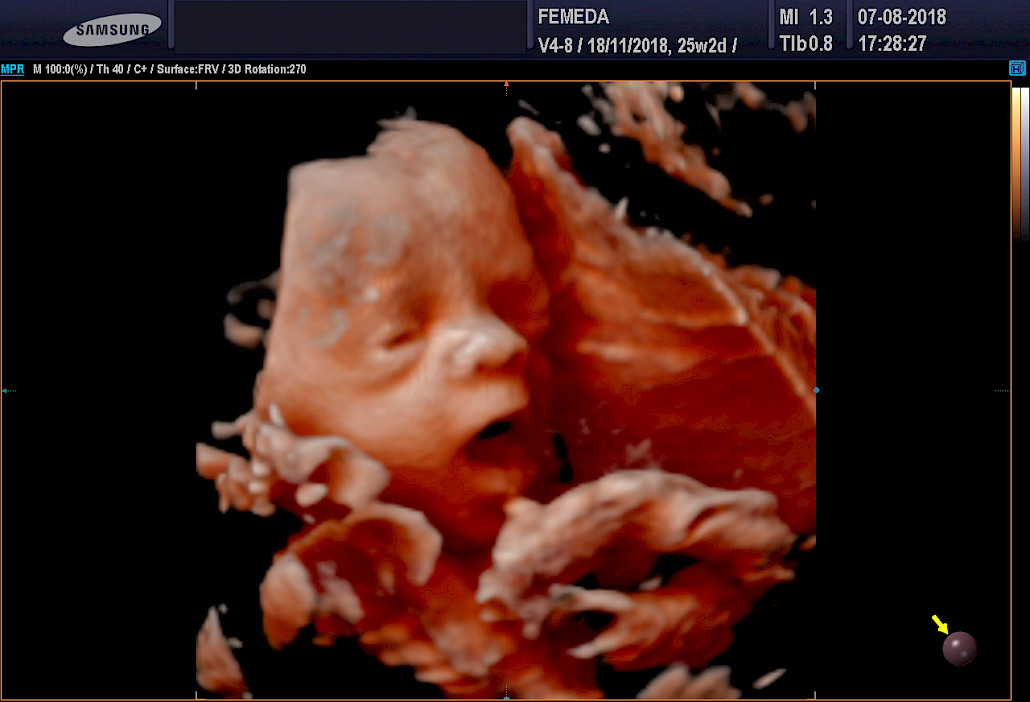

Kuva Femedan 4D-ultraäänitutkimuksesta

3D ja 4D-tekniikat soveltuvat erityisen hyvin sikiön kasvojen anatomian tutkimiseen. Tutkimuksessa poissuljetaan mahdollinen huulihalkio ja kasvojen profiilissa esiintyvät muut poikkeamat, kuten liian pieni leuka. Samalla selvitetään korvien anatomia ja niiden sijainti. Tekniikan avulla selvitetään raajojen asennot, sekä sormien ja varpaiden lukumäärä ja niiden liikkuvuus. Lisäksi tutkitaan koko selkärangan rakenne ja suljetaan pois poikkeamat, kuten puuttuvat lapa- tai olkaluut.